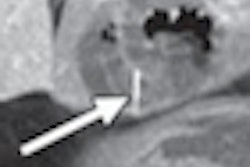

Flat colorectal polyps, which tend to harbor high-grade dysplasia more often than polypoid lesions, are hard to detect at virtual colonoscopy -- that is, unless they're run through a computer-aided detection (CAD) algorithm developed by Harvard Medical School researchers.

In a study presented last month at the 2012 European Congress of Radiology (ECR), the Harvard team found no significant difference in the detection rate for polypoid versus flat lesions in the CAD scheme trained and tested on thousands of screening subjects. False positives were kept on the low side, as well, the group reported. Get the details on these suddenly less elusive lesions in this issue's Insider Exclusive.